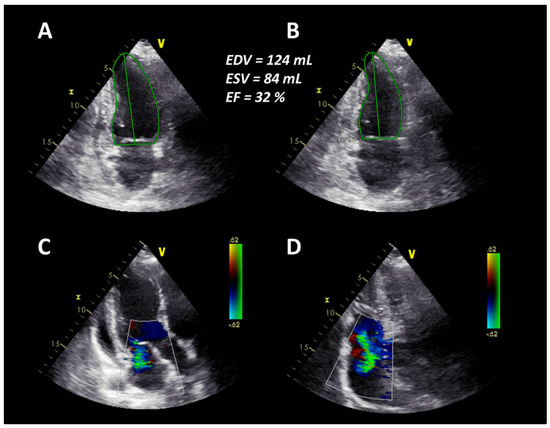

In April 2019, six months after AHSCT, the patient was readmitted due to unusual weakness, fatigue, and newly developed leg edema with a mRSS of 11 points (Figure 1). Laboratory testing revealed elevated NT-proBNP value of 11,189 pg/mL. Echocardiography revealed an LVEF of 32% and pericardial effusion as well as newly developed mitral and tricuspid regurgitation corresponding to acute heart failure (Figure 3).

At the same time, CT changes and spirometric lung function parameters slightly improved. Subsequently, heart failure treatment was intensified with carvedilol, thiazide diuretics, and a higher dose of ACE inhibitors, resulting in concomitant improvement of cardiac parameters. Due to further progression of the disease—despite AHSCT—the patient started on monotherapy with RTX in July 2019. In August 2019, after completion of the first cycle of RTX, clinical symptoms and spirometry parameters ameliorated noticeably (FVC 72.5% predicted, FEV1 79.2% predicted, FEV1/FVC ratio 89.8%), conversely DLCO slightly deteriorated to 38.2% predicted (Figure 1). In October 2019, after completion of the second cycle of rituximab, lung function (FVC 91% predicted, FEV1 95% predicted, FEV1/FVC ratio 84%, DLCO 44% predicted) and mRSS (1 point) further improved significantly (Figure 1). There was also a significant improvement of the echocardiographic findings to a LVEF of 52%, no mitral regurgitation and mild tricuspid regurgitation (Figure 4). Additionally, NT-proBNP levels decreased to 2289 pg/mL.

Figure 3. (A) End-diastolic borders of the left ventricle in the apical two-chamber view. (B) End-systolic borders of the left ventricle in the apical two-chamber view. (C) Mild to moderate mitral regurgitation in the apical three-chamber view. (D) Moderate tricuspid regurgitation in the apical four-chamber view.